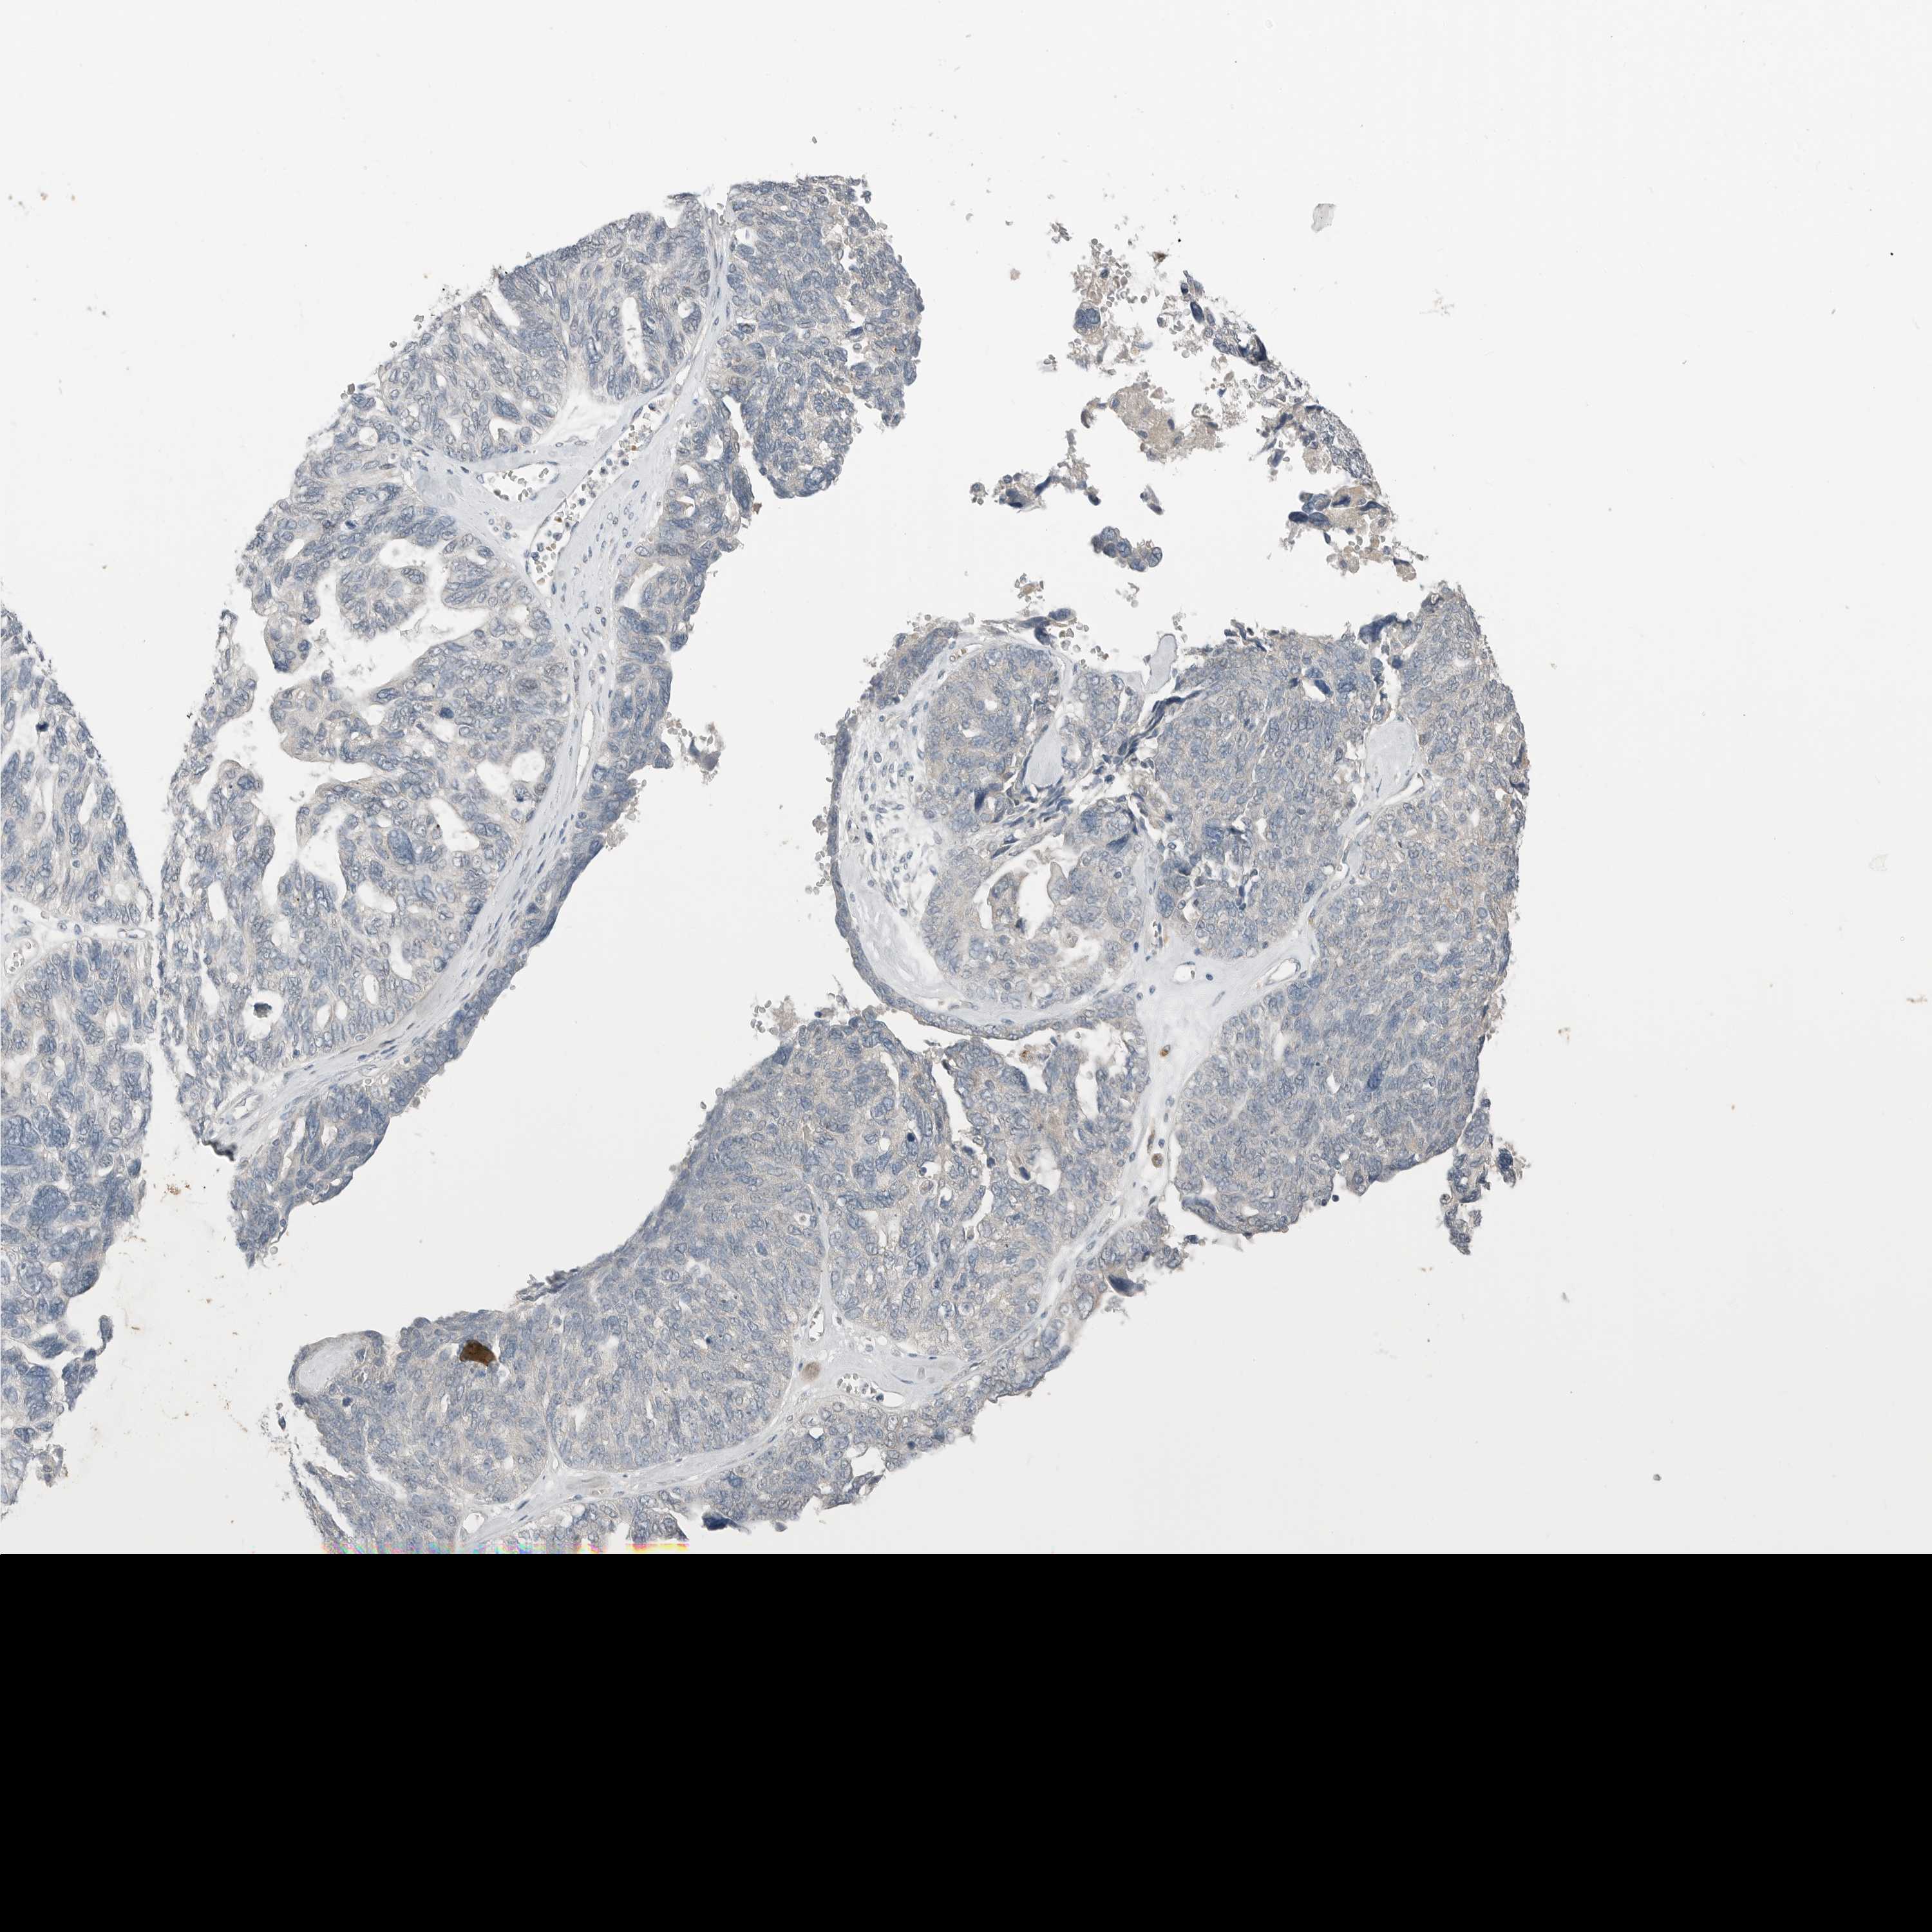

OVARIAN CANCER - Protein expressioni

A mouse-over function shows sample information and annotation data. Click on an image to view it in a full screen mode. Samples can be filtered based on level of antibody staining by selecting one or several of the following categories: high, medium, low and not detected. The assay and annotation is described here.

Note that samples used for immunohistochemistry by the Human Protein Atlas do not correspond to samples in the TCGA dataset.

Antibody stainingi

Antibody staining in the annotated cell types in the current human tissue is reported as not detected, low, medium, or high, based on conventional immunohistochemistry profiling in selected tissues. This score is based on the combination of the staining intensity and fraction of stained cells.

Each image is clickable and will lead to virtual microscopy that enables deeper exploration of all samples and also displays staining intensity scores, fraction scores and subcellular localization as well as patient and tissue information for each sample.

Antibody CAB026139

Staining

High

Medium

Low

Not detected

Intensity

Strong

Moderate

Weak

Negative

Quantity

>75%

75%-25%

<25%

None

Location

Nuclear

Cytoplasmic/membranous

Cytoplasmic/membranous,nuclear

Cystadenocarcinoma, serous, NOS

Carcinoma, endometroid

Cystadenocarcinoma, mucinous, NOS

Carcinoma, NOS